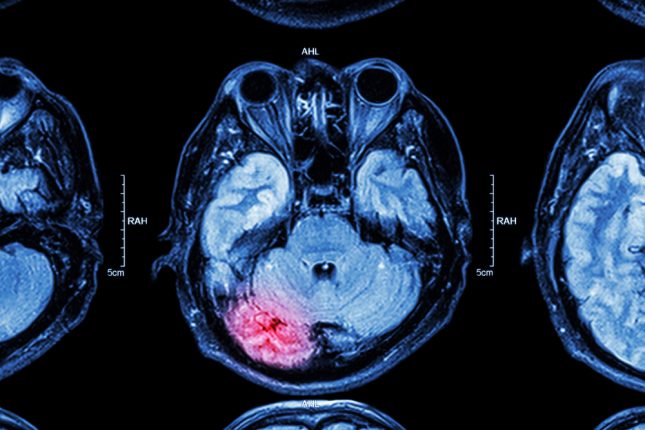

לפי מחקר חדש, שינויים בכלי דם במוח שנגרמים כתוצאה מפגיעת ראש יכולים להיות הטריגר הראשוני להתפתחות מחלות נוירו-דגנרטיביות

חבלת-ראש.-אילוסטרציה

טראומה מוחית פוגעת בדרך כלל בזרימת הדם למוח. אחת התיאוריות היא שהטראומה גורמת לפגיעה בתאים המרכיבים את דפנות כלי הדם. כתוצאה מכך, נוצרת הפרעה בזרימת הדם בתוך העורקים, אשר יכולה להוביל להחמרת הנזק המוחי. עם זאת, כיום לא ידועים המנגנונים בהם מתרחש אפקט זה.

החוקרים גילו שכתוצאה מהחבלה נוצרו שינויים בתאים המרכיבים את דפנות כלי הדם, ואלו עודדו הצטברות של חלבון הקרוי "עמילואיד בטא" בכלי הדם. עמילואיד בטא הוא חלבון שידוע כשחקן ראשי בהתפתחות מחלת האלצהיימר. במחלה הוא נוטה להצטבר ולשקוע ברקמת המוח ולפגוע בתפקוד שלה. כתוצאה מכך, החולים סובלים מירידה בתפקוד הקוגניטיבי ובזיכרון.